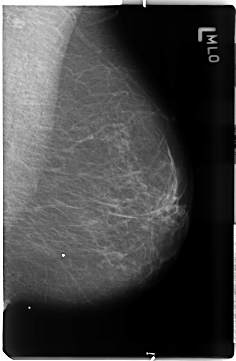

B_3506_1.LEFT_MLO

LEFT_MLO LINES 4688 PIXELS_PER_LINE 3056 BITS_PER_PIXEL 12 RESOLUTION 50 NON_OVERLAY